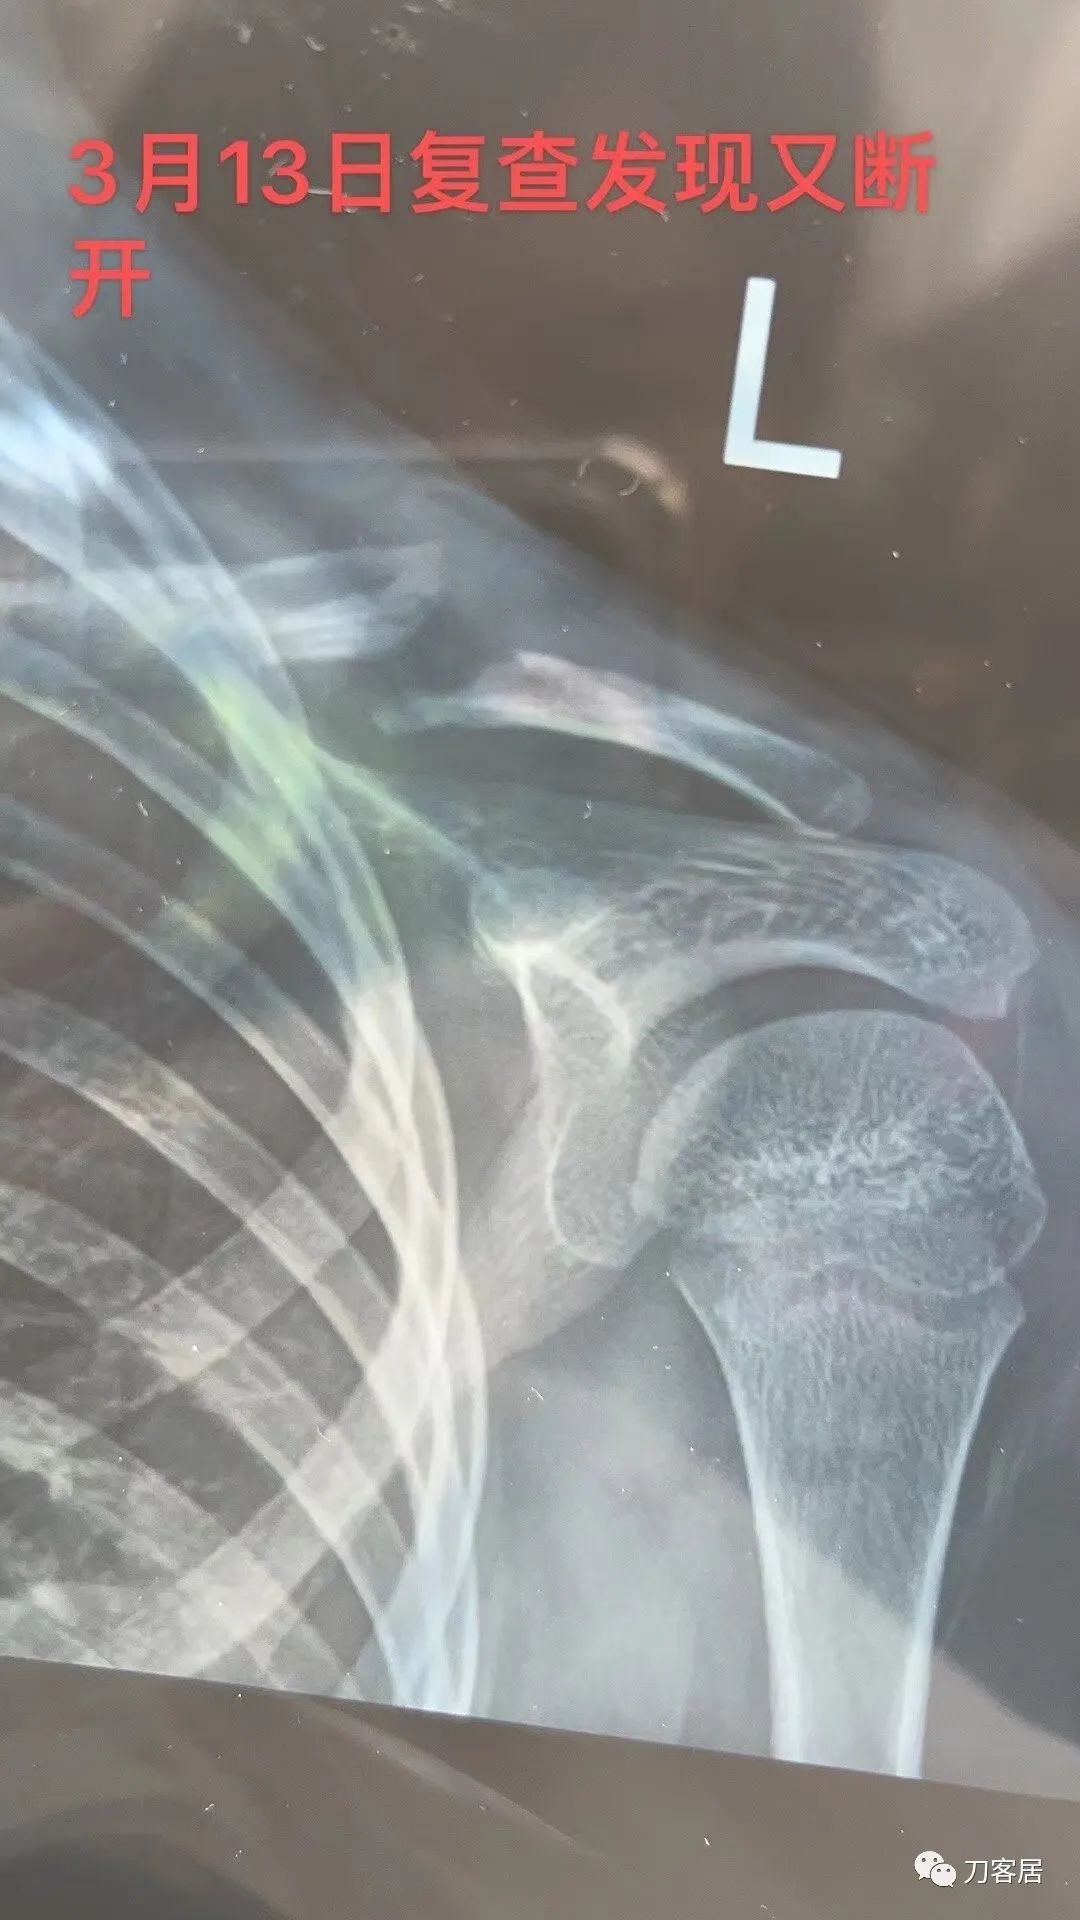

大家都很敬业苦口婆心,奈何家属可能不理解,我提供个反面教材给看看手术失败病例,也让家属感受一下。

网络问诊的病例,没有后续,但觉得孩子很无辜!

ZRH 10:46

为啥要急着拔针?针留在皮外?

网络问诊的病人,我也不知道那个医院为啥要这么快拔针[难过],应该是术后8周,见骨痂生长,皮外针尾也有刺激,就考虑拔针了。

目前这个病人从片子上看确实得要植骨了,骨不连很明显了,髓腔断端看上去也很圆滑,似乎已经闭合了[捂脸]。

儿童锁骨骨折罕见不愈合,这个孩子锁骨骨折不愈合,与手术广泛剥离,骨膜损伤有关系。

保守治疗几乎没有不愈合的。

应该是切开复位的,克氏针的尖都去掉了,闭合复位就很难穿进去,只是不知道剥离了多少。

看术后片子,术者可能是切开手术。

不愈合的话,估计是切开复位的[微笑],我目前还没有见到过闭合复位不愈合的病人。

Figure 6-8 Although rare, clavicle nonunions can occur in children.

虽然罕见,但小儿锁骨骨折确实有骨不连发生的可能。

Although non-unions have been reported in as many as 15% of completely displaced clavicle fractures in the adult population, they remain an extremely rare complication in pediatric patients with less than a dozen cases having been reported in the literature (Fig. 6-8). Over the last 10 years, our institution has treated hundreds of midshaft clavicle fractures and we have only observed three non-unions all of which were successfully managed with local bone graft and plate fixation. We, therefore, do not believe that nonunion concerns in adolescent patients, even with displaced fracture patterns, justify acute surgery.

尽管成人完全移位的锁骨骨折存在15%的不愈合,但儿童患者完全移位的锁骨骨折不愈合极为罕见,文献报道的病例不到十几例(图6-8)。过去10年里,本单位治疗的数百例锁骨中段骨折,只有3例骨折不愈合,所有这些骨折不愈合均通过局部植骨和钢板固定成功治愈。因此,我们不认为青少年患者的锁骨骨折骨不连是个问题,即使骨折移位,也不能作为急性手术的理由。